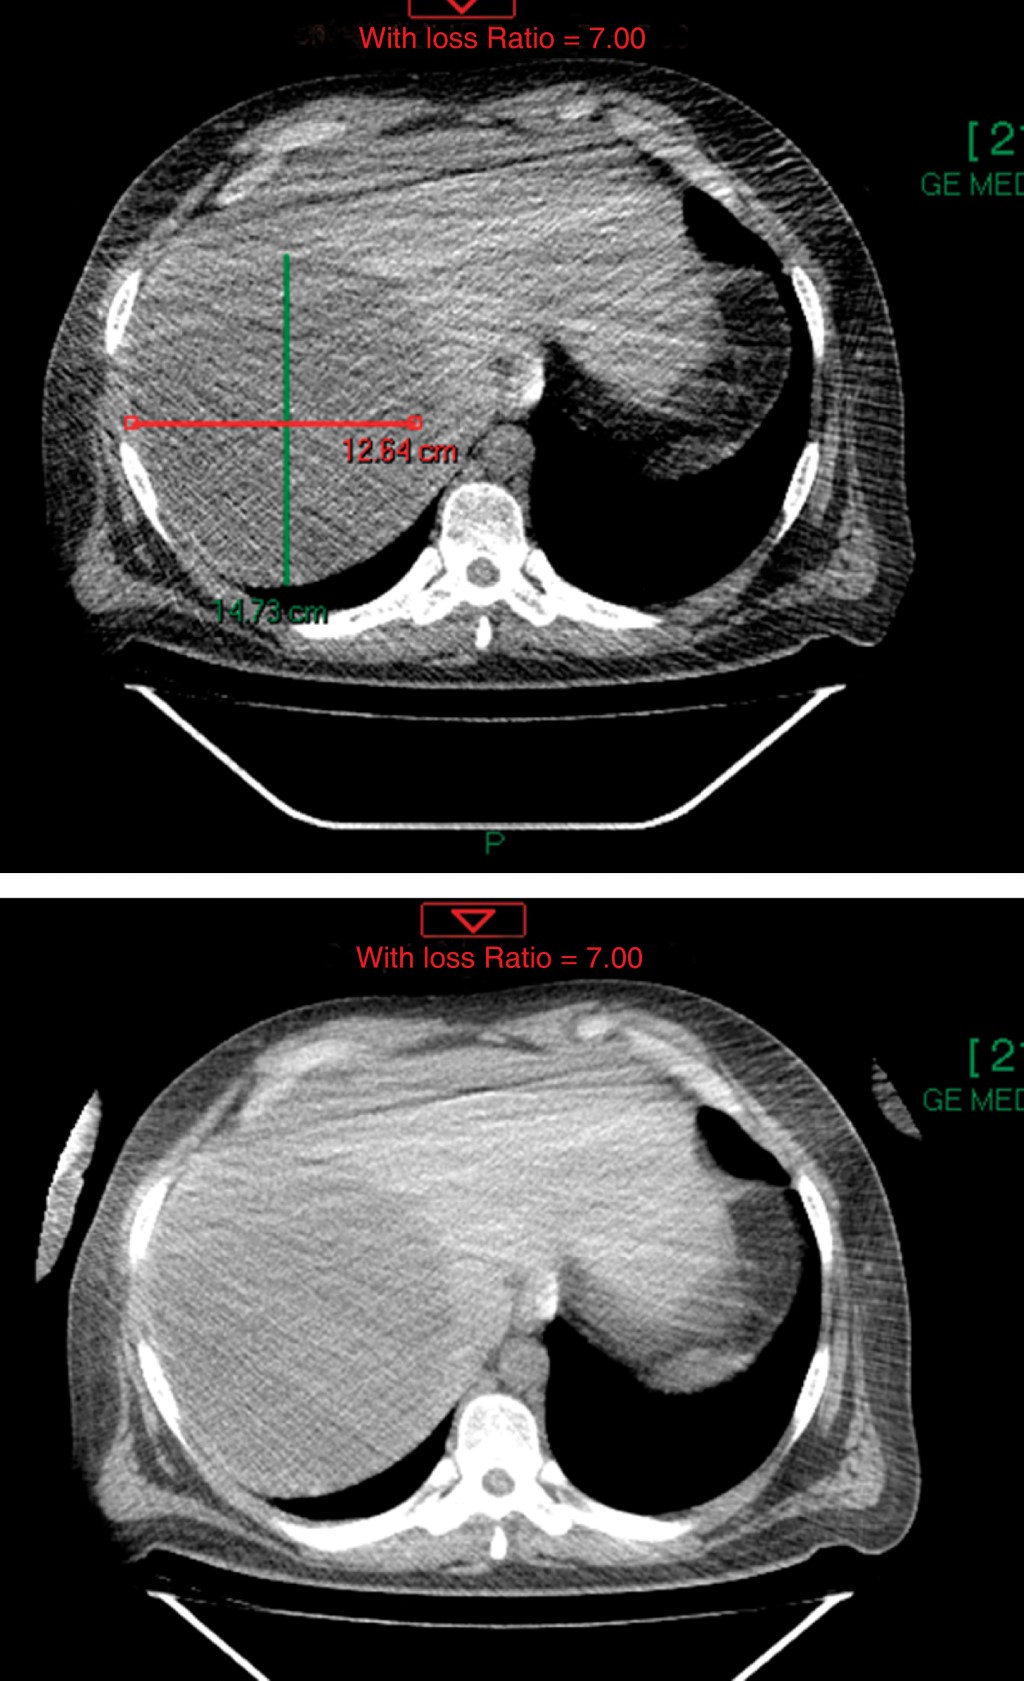

A su ingreso se mostraba ansioso, alerta, orientado; valoración inicial ATLS (Advanced Trauma Life Support), sin compromiso hemodinámico, neurológicamente sin déficit, tórax con dermoabrasiones, campos ventilados de manera bilateral, hipoventilación basal de hemitórax derecho, abdomen con marcas cutáneas de neumáticos, blando, depresible con dolor a la palpación generalizada profunda, datos de irritación peritoneal en cuadrantes inferiores, extremidades con dermoabrasiones en antebrazos. Se realizan placas de protocolo de ATLS, se observó en la radiografía de tórax (Figura 1) hemitórax derecho con elevación del hemidiafragma, sin neumotórax o derrame pleural, se efectúa FAST (Focused Abdominal Sonography for Trauma) primario sin revelar líquido en pericardio, espacio hepatorrenal, esplenorrenal o en pelvis, se realiza tomografía axial computarizada simple y contrastada toraco-abdomino-pélvica (Figuras 2 y 3) en la que se observa imagen compatible con quiste hepático simple de 12.6 x 14.7 cm.

Figura 2